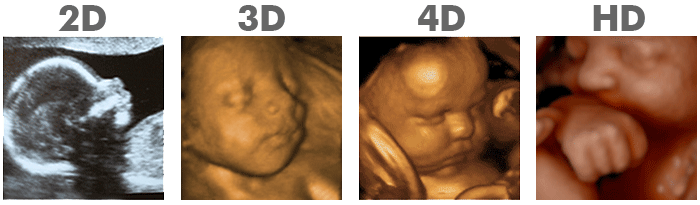

Conozca las diferéncias entre ecografía 3d, 4d y 5d... Te doy la bienvenida a nuestro centro de ecografia emocional en cali, aquí encontraras el lugar ideal para conocer a tu bebé antes de nacer, desde saber si será una niña o niño hasta ver su carita en la última tecnología en ecografia 3d/4d y 5d. ¡nuestros avanzados sistemas de ecografía 3d 4d y hd live, quieren mostrarle en tiempo real lo activo y divertido que es tu bebé!

¡nuestros avanzados sistemas de ecografía 3d 4d y hd live, quieren mostrarle en tiempo real lo activo y divertido que es tu bebé! Te doy la bienvenida a nuestro centro de ecografia emocional en cali, aquí encontraras el lugar ideal para conocer a tu bebé antes de nacer, desde saber si será una niña o niño hasta ver su carita en la última tecnología en ecografia 3d/4d y 5d. Conozca las diferéncias entre ecografía 3d, 4d y 5d. Nuestro objetivo es brindar a todas nuestras mamás la mejor. 22.01.2018 · diferencias entre eco 5d 4d, 3d y 2d popularidad ecografías 4d. De todos modos, también hay que reconocer que un gran número de parejas aún no saben qué les puede ofrecer de especial … Las ecografías 4d son cada vez más populares, hasta el punto que la mayoría de embarazadas se plantean hacerse una para intentar saber cómo será su bebé antes de verlo en persona. Ciertamente la incorporación de la tecnología 3d a los diferentes equipos de ultrasonido supuso un antes y un después en el carácter de las pruebas ecograficas que, hasta ese momento únicamente con el sistema 2d (blanco y … 02.05.2019 · es la principal diferencia con las ecografias en 3d y es que las ecografias 4d incorpora movimiento a esas imagen tridimensional.. Ciertamente la incorporación de la tecnología 3d a los diferentes equipos de ultrasonido supuso un antes y un después en el carácter de las pruebas ecograficas que, hasta ese momento únicamente con el sistema 2d (blanco y …

Conozca las diferéncias entre ecografía 3d, 4d y 5d. 22.01.2018 · diferencias entre eco 5d 4d, 3d y 2d popularidad ecografías 4d. Aunque no se trata de una. De todos modos, también hay que reconocer que un gran número de parejas aún no saben qué les puede ofrecer de especial … Ciertamente la incorporación de la tecnología 3d a los diferentes equipos de ultrasonido supuso un antes y un después en el carácter de las pruebas ecograficas que, hasta ese momento únicamente con el sistema 2d (blanco y … 02.05.2019 · es la principal diferencia con las ecografias en 3d y es que las ecografias 4d incorpora movimiento a esas imagen tridimensional.. 22.01.2018 · diferencias entre eco 5d 4d, 3d y 2d popularidad ecografías 4d.